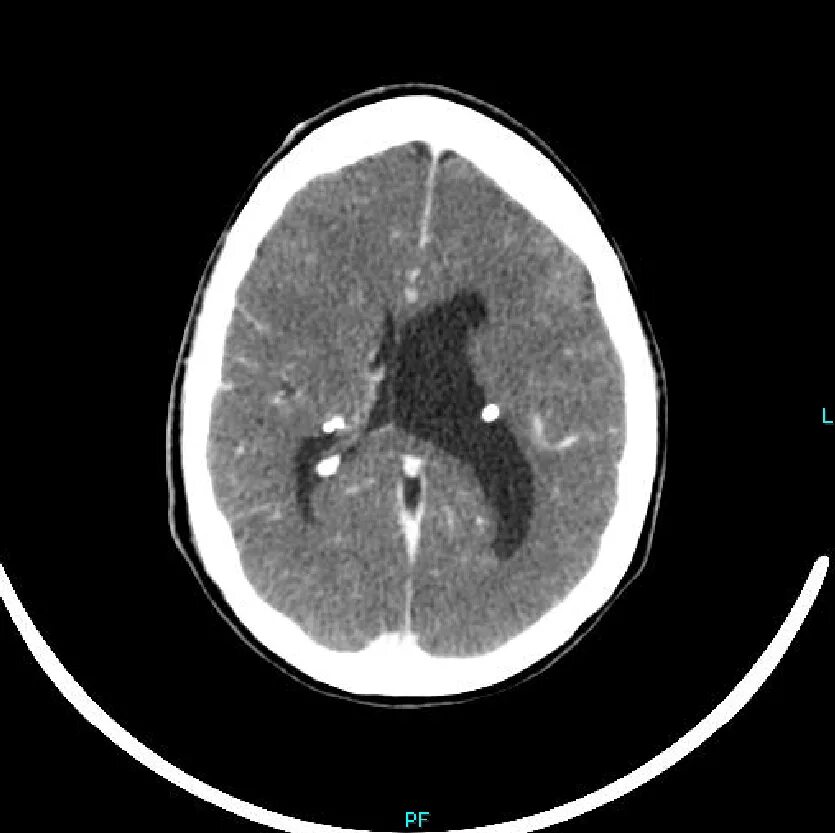

Туберкулезный склероз